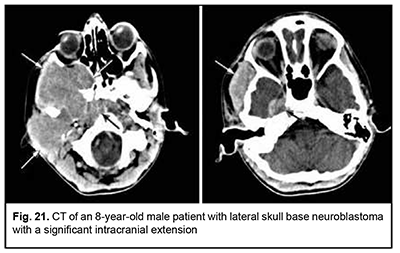

Neuroblastoma originates from neural crest cells of the the sympathetic nervous system, has an aggressive course and invasive growth pattern, and can grow to giant sizes (Fig. 21). Discussion ASBOT arise from the head-and-neck tissues, particularly, (1) bone and cartilage tissues; (2) orbit tissue; (3) facial and hairy scalp skin; (4) remnants of the notochord; (5) nasal cavity mucosa and paranasal sinus mucosa; (6) lining and glandular epithelium; (7) dura mater; and (8) vessels, nerves and sympathetic ganglia [13]. Most ASBOT are the tumors originating in the nasal cavity and paranasal sinuses and extending to and growing into the skull base, and extending intracranially. Nasal cavity and paranasal sinus tumors are commonly malignant [11, 14]. With regard to the origin and extension of benign ASBOT, it has been reported that craniofacial osteomas are tumors with intracranial growth and multidirectional extensions affecting anterior skull base bones [14], whereas meningiomas had primary intra- and extracranial growth at the sites of ethmoid labyrinth, medial middle cranial fossa and medial posterior cranial fossa [14-18], which is in agreement with our findings. Our findings with regard to malignant ASBOT are close to those of others who have reported that adenocarcinomas, unspecified cancers and adenoid cystic carcinomas are malignant tumors characterized by early intracerebral and intracranial invasion with an aggressive course. In addition, these cancers are characterized by continuous invasive growth with extension into the orbit where the tumor grows into the periorbit and orbital fat. These tumors have an unfavourable prognosis for survival [5, 11, 19-24]. The current study demonstrated that an intracranial extension with destruction of the roof and external wall of the orbit is also seen in PELGT that originate in the orbit and exhibit aggressive and recurrent growth [6, 7-10, 12, 25]. The course of cancers of other origins (neuroblastoma, leiomyosarcoma, osteoblastoclastoma, chondrosarcoma) is not less malignant than that of the above cancers. They have an aggressive course and invasive growth pattern, and can grow to giant sizes and extend intradurally and intracerebrally, showing fusion with surrounding tissues [26-31]. According to our findings and those of others, such benign tumors of cartilage origin as chordoma and chondroma grow slowly, show slow and expansive growth, and extend centrally. However, chondroma may undergo malignant transformation to chondrosarcoma and have a recurrent course [11, 19, 29-31]. The expansive growth of these tumors is accompanied by bony destruction with intradural or subdural extensions [28, 31, 32]. Patients with esthesioneuroblastoma tend to have better survival rates than those with other malignant ASBOT if early treated with radical surgery and effective combination therapy [12, 18, 33-36]. Therefore, large and even giant size is a common feature of ASBOT; this is true also for primary tumors diagnosed for the first time. On the basis of the analysis of patient complaints and clinical aspects and comparison of this data with imaging data, we found that ASBOT have a long asymptomatic stage. In addition, we broadly categorized patient complaints into cerebral, rhynologic, neuro-ophthalmologic and otologic, and found that these complaints were almost as common in patients with benign as with malignant ASBOT. The nature of complaints depended on tumor extension to relevant cerebral and skull base structures. We also determined frequencies of injury to various compartments of the intra- and extra-cranial surfaces of the skull base for benign and malignant processes. Compared with malignant ASBOT, benign ASBOT were found to be more commonly located in the lateral skull base (with a rate as high as 40.6%). Malignant ASBOT were more commonly seen within the floor of the anterior cranial fossa (77.2%). There are certain grades of intracranial growth for malignant ASBOT and intracranial extension for benign ASBOT, these grades depending mostly on histobiological characteristics and disease duration. Adenocarcinoma originating in the lacrimal gland is the most aggressive form of epithelial cancer of the orbit with a rate of mortality of 67.7%. While growing, it causes destruction of the roof and external wall of the orbit with extension into the temporal fossa and cranial cavity and involvement of the cerebrum.